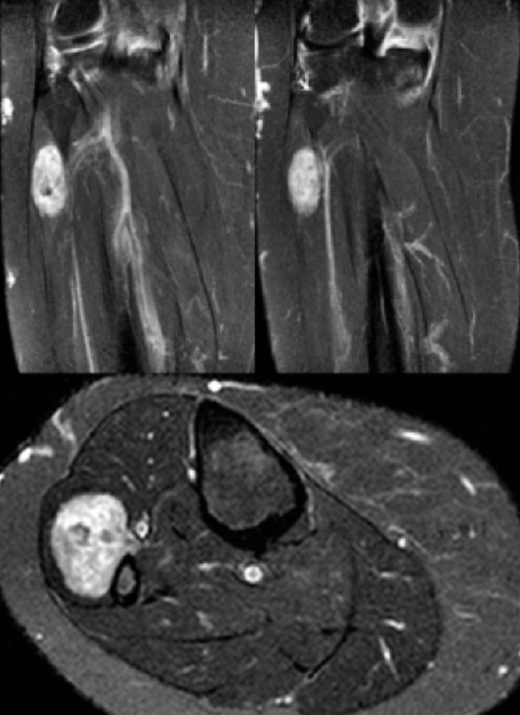

Se trata de una mujer de 78 años que consulta por imposibilidad para la extensión y limitación de la movilidad del hallux del pie derecho de 2 años de evolución desde una intervención quirúrgica en la rodilla derecha por un schwannoma al nivel del CPE (Figura 1).

Figura 1. Schwannoma en el ciático poplíteo externo intervenido en marzo de 2017 (realizan neurectomía con disección intraneural y resección intralesional-marginal).